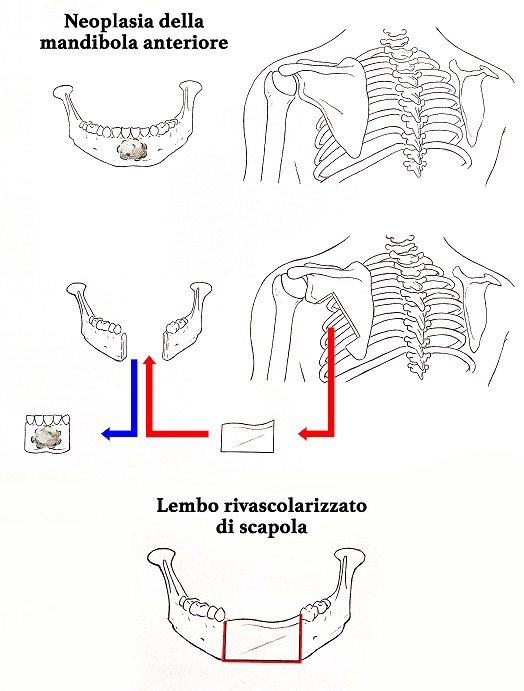

L`equipe dell`Unità di Otorinolaringoiatria dell`Istituto Nazionale Tumori Regina Elena, diretta da Raul Pellini, ha asportato un esteso tumore dell`arco della mandibola, con contestuale ricostruzione chirurgica, alla signora M. di 87 anni che ha superato in modo brillante il delicato intervento durato 8 ore. “E` necessario ricostruire il deficit osseo per garantire una buona qualità di vita al paziente, specie quando particolarmente fragile e più esposto a complicanze. La rimozione dell`arco anteriore mandibolare – spiega Raul Pellini – comporta un difetto funzionale ed estetico molto invalidante”.

“Siamo molto soddisfatti della riuscita dell`intervento che è sofisticato e molto raramente può essere effettuato in pazienti di età così avanzata – prosegue Pellini – . Solitamente la sede donatrice di tessuto è la gamba, che offre una porzione di osso più idonea alla ricostruzione e consente a due equipe chirurgiche di lavorare contemporaneamente. In questo caso la paziente, presentava però difficoltà alla deambulazione legate all`età e a una fisiologica degenerazione articolare. Abbiamo scelto, in accordo con la paziente e dopo consulto con i familiari, di prelevare l`osso donatore dalla scapola, nonostante le maggiori difficoltà tecniche ed esecutive”.

“Il lembo di osso prelevato dalla scapola – spiega Raul Pellini – è stato rivascolarizzato e mediante tecniche microchirurgiche alle arterie e alle vene del collo, per ripristinare l`aspetto estetico e soprattutto funzionale, ricostruendo i tessuti asportati per la neoplasia.” (vede foto) In generale gli interventi di questo tipo hanno un importante impatto funzionale sull`alimentazione rischiando di sbilanciare il già precario equilibrio di questo tipo di pazienti.